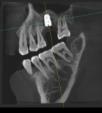

口腔检查 :全口咬合关系基本正常。26缺失,缺失区牙槽骨丰满度良好,颊舌向宽度约9mm。牙龈状况良好,无溃疡红肿。缺牙区邻牙未见明显倾斜,合龈高度约6mm。 CBCT显示:26缺失,骨质III类,缺牙区牙槽嵴宽度约9mm,牙槽嵴距离上颌窦底为6-7mm,窦嵴距不足。

诊断:26牙缺失;  治疗:26牙行种植修复(经牙槽嵴上颌窦提升术)  治疗方式:术区行利多卡因+布比卡因阻滞麻醉,碧兰麻行浸润麻醉。常规消毒铺单,待麻药显效后,于26牙槽嵴顶做近远中切口,剥离术区黏骨膜,26远中做颊侧附加切口,显露术野。生理盐水冲洗冷却下大球钻修整骨面,小球钻确定26种植位点。先锋钻确定种植体植入方向,扩孔钻逐级扩大种植窝洞,窝洞预备至接近上颌窦底,插入深度测量尺观测深度与方向,扩孔钻扩大种植窝洞。使用上颌窦底冲压骨凿,轻敲骨凿底部至10mm,做鼻腔鼓气试验,检查上颌窦黏膜完整性,最终植入种植体,查种植体方向和初期稳定性良好,旋入覆盖螺丝。严密缝合创口。常规止血,术毕。